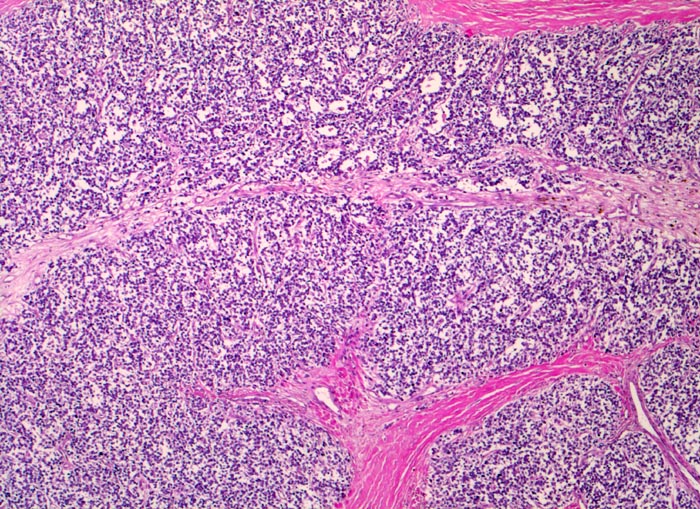

Die Tumoren sind makroskopisch grauweiss und wachsen destruktiv und infiltrativ. Nekrosen und Einblutungen sind häufig. Histologisch lassen sich solide Rasen monomorpher, kleiner, rundlicher Tumorzellen mit dichtem Chromatin und wenig Zytoplasma nachweisen (sog. small-blue-round cells). Metastasen treten vor allem in der Lunge und in anderen Skelettabschnitten auf. Die Differentialdiagnose klein-blau- und rundzelliger Tumoren im Kindesalter ist breit. Kleinzellige Osteosarkome, Neuroblastome, Lymphome und mesenchymale Chondrosarkome können ein histologisch ähnliches Bild zeigen, speziell in kleinen Biopsien, und müssen mit Hilfe von (molekularen) Zusatzuntersuchungen und unter Einbezug klinischer und radiologischer Befunde voneinander abgegrenzt werden.

• Durch Bindegewebssepten abgegrenzte Knoten (lobuläre Architektur).

• Blauer, klein- und rundzelliger Tumor.

• Uniforme Zellen mit schmalem, kaum abgrenzbarem Zytoplasmasaum und unscharfen Zellgrenzen. Rundliche oder ovale Zellkerne mit leicht vergröbertem Chromatin und punktförmigen kleinen Nukleolen.

• Quetschartefakte (gequetschte Zellen sind dunkler und haben verkleinerte abgeflachte Zellkerne).